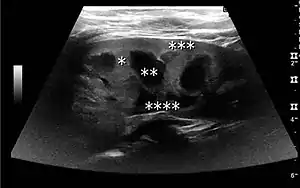

Figure 1. Normal adult kidney. Measurement of kidney length on the US image is illustrated by ‘+’ and a dashed line. *Column of Bertin; ** pyramid; *** cortex; **** sinus.[1]

The kidney is divided into parenchyma and renal sinus. The renal sinus is hyperechoic and is composed of calyces, the renal pelvis, fat and the major intrarenal vessels. In the normal kidney, the urinary collecting system in the renal sinus is not visible, but it creates a heteroechoic appearance with the interposed fat and vessels. The parenchyma is more hypoechoic and homogenous and is divided into the outermost cortex and the innermost and slightly less echogenic medullary pyramids. Between the pyramids are the cortical infoldings, called columns of Bertin (Figure 1). In the pediatric patient, it is easier to differentiate the hypoechoic medullar pyramids from the more echogenic peripheral zone of the cortex in the parenchyma rim, as well as the columns of Bertin (Figure 2).[1]

Cortical thickness should be estimated from the base of the pyramid and is generally 7–10 mm. If the pyramids are difficult to differentiate, the parenchymal thickness can be measured instead and should be 15–20 mm (Figure 3). The echogenicity of the cortex decreases with age and is less echogenic than or equal to the liver and spleen at the same depth in individuals older than six months. In neonates and children up to six months of age, the cortex is more echogenic than the liver and spleen when compared at the same depth.[1]